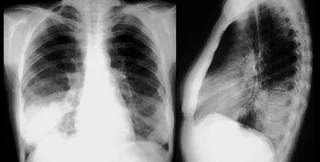

Как известно, человеческое легкое представляет собой сложное инженерное решение, созданное природой: площадь поверхности одного легкого у взрослого человека составляет около 70 квадратных метров, "упакованных" так, чтобы обеспечивать эффективный перенос кислорода и углекислого газа между кровью и воздухом. Однако ткань легкого трудно восстанавливать, и сейчас единственный способ заменить поврежденные участки органа - пересадка. Она сопряжена с высокими рисками отторжения органа и инфекции, поэтому через 10 лет после операции остаются в живых лишь 10-20% пациентов.

Как сообщает РИА Новости, группа ученых Йельского университета под руководством Лауры Никласон вырастила в лаборатории клетки легкого и пересадила на "каркас" органа у взрослых крыс, где клетки действовали подобно настоящим. "Нам удалось разработать и изготовить пригодное для пересадки крысам легкое, эффективно переносящее кислород и углекислый газ и оксигенирующее гемоглобин в крови. Это один из первых шагов на пути к воссозданию целого легкого у более крупных животных и в конечном итоге у человека", - сказала Никласон.

Группа Никласон удалила из легких взрослой крысы клеточные компоненты, оставив ветвистые структуры легочных путей и кровеносные сосуды, которые послужили "каркасом" для новых легких. Ученые в лабораторных условиях вырастили клетки легкого, используя новый биореактор, имитирующий процесс развития легких у эмбриона, и высадили на подготовленный "каркас".

Высаженные клетки заполнили внеклеточный матрикс - структуру ткани, обеспечивающую механическую поддержку и перенос веществ. Пересаженные крысам на 45-120 минут, эти искусственные легкие поглощали кислород и выводили углекислый газ подобно настоящим. "Хотя это лишь первый шаг к конечной цели - созданию полностью функциональных легких в лабораторных условиях, наши результаты предполагают, что заполнение клетками легочной матрицы - технически осуществимая стратегия восстановления легкого", - заявили ученые.